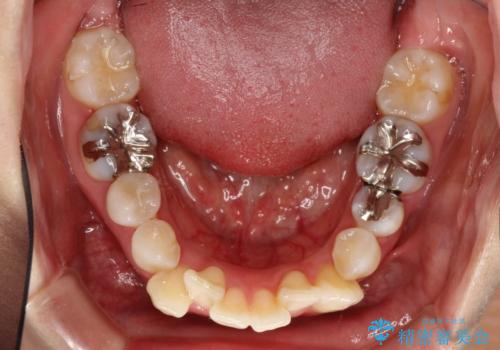

目立たないハーフリンガル矯正 抜歯矯正で口元を改善

- 前歯のデコボコと上顎の前突感による口の閉じにくさを気にして来院された患者様です。

目立たない装置を希望されたので、上顎が裏側装置のハーフリンガルを選択し、上下左右の小臼歯(計4歯)を抜歯して矯正治療を行うこととしました。

治療期間の目安は3年~3年半でしたが、咬み合わせにより上顎のスペースがなかかな閉じきらず、治療期間が長期化してしまいました。